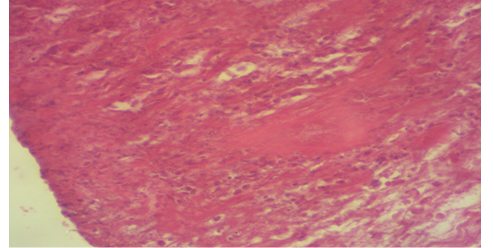

Photomicrography of T1 group of 15th days post operation showed scar tissue and irregular fibrosis at the wound area (H&E 100X).